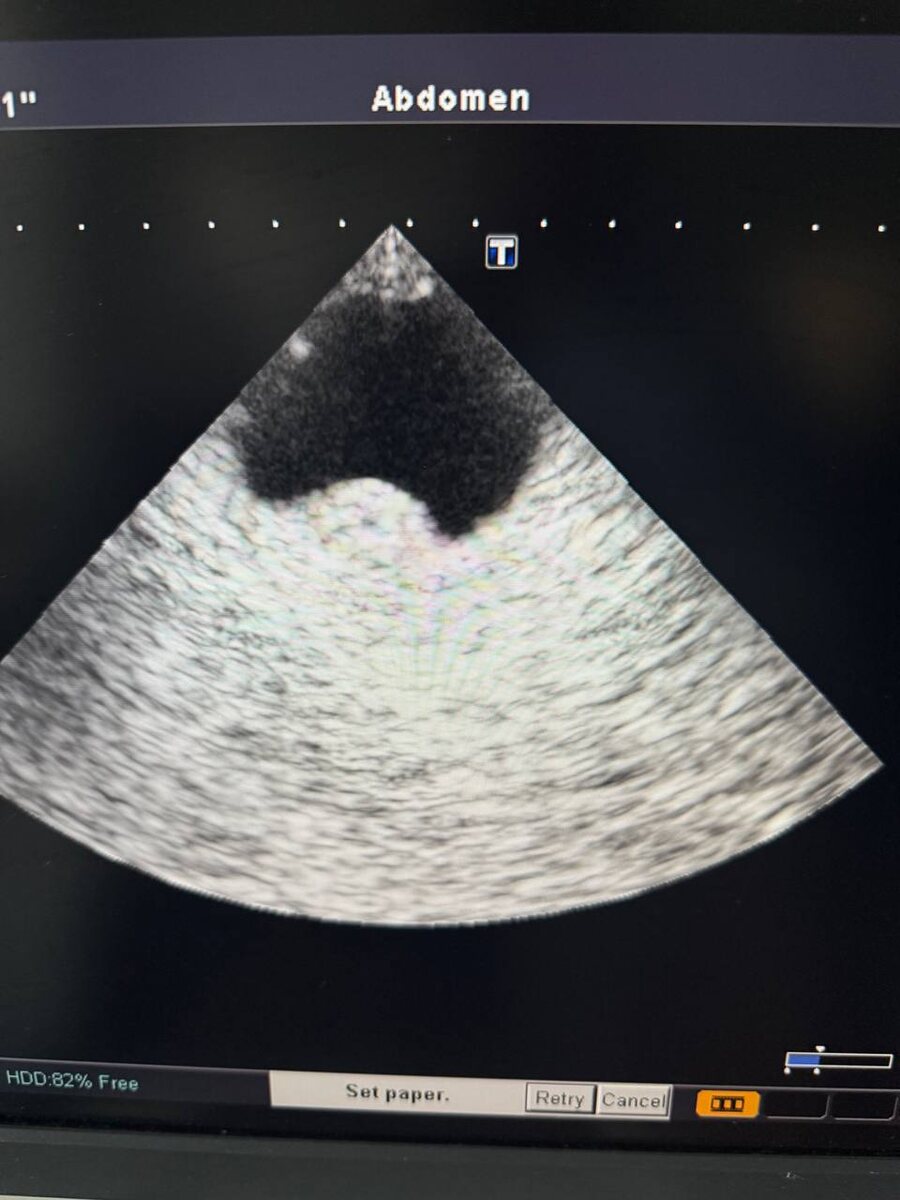

На днях случился клин случай. В неотложку обращается пациент около 30 лет. Внезапно утром ослеп глаз один. Проблем со зрением никогда не было. Из анамнеза в марте или апреле удаление злокачественного новообразования, затем химия. То ли пациент чего-то недоговаривает, то ли недообследован оказался. В общем причина снижения зрения в наличии + ткани в заднем полюсе глаза. Ну и сделали скт на всякий, в головном мозге также несколько очагов отсева. Вряд ли первичные, скорее метастазы. За глаз тут уже бороться бесполезно по большому счету. За жизнь только если и то может быть…

На днях случился клин случай. В неотложку обращается пациент около 30 лет. Внезапно утром ослеп глаз один. Проблем со зрением никогда не было. Из анамнеза в марте или апреле удаление злокачественного новообразования, затем химия.

То ли пациент чего-то недоговаривает, то ли недообследован оказался. В общем причина снижения зрения в наличии + ткани в заднем полюсе глаза. Ну и сделали скт на всякий, в головном мозге также несколько очагов отсева. Вряд ли первичные, скорее метастазы.

За глаз тут уже бороться бесполезно по большому счету. За жизнь только если и то может быть…